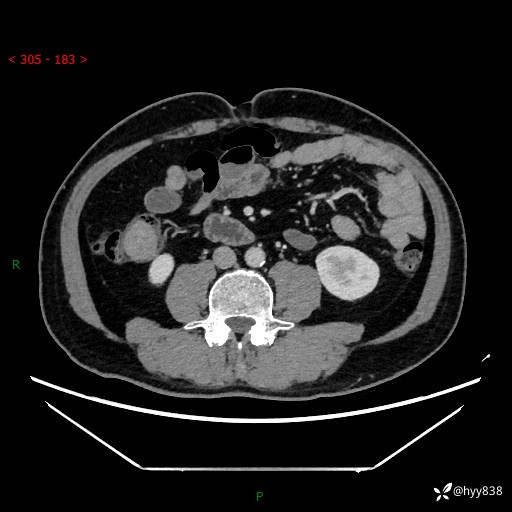

腹部CT增强扫描(外院CT平扫)

两期CT值:75hu 82hu